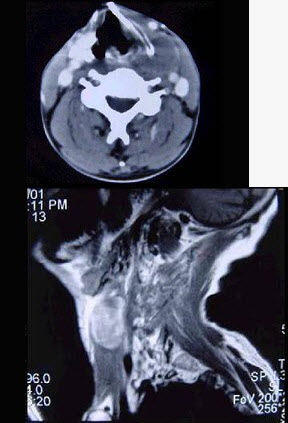

男性,40岁,发现左侧颈部小包块,CT、MRI检查如图所示,请选择最可能的诊断()。

A、神经鞘瘤

B、神经纤维瘤

C、海绵状血管瘤

D、肿大淋巴结

E、副神经节瘤

正确答案:

C